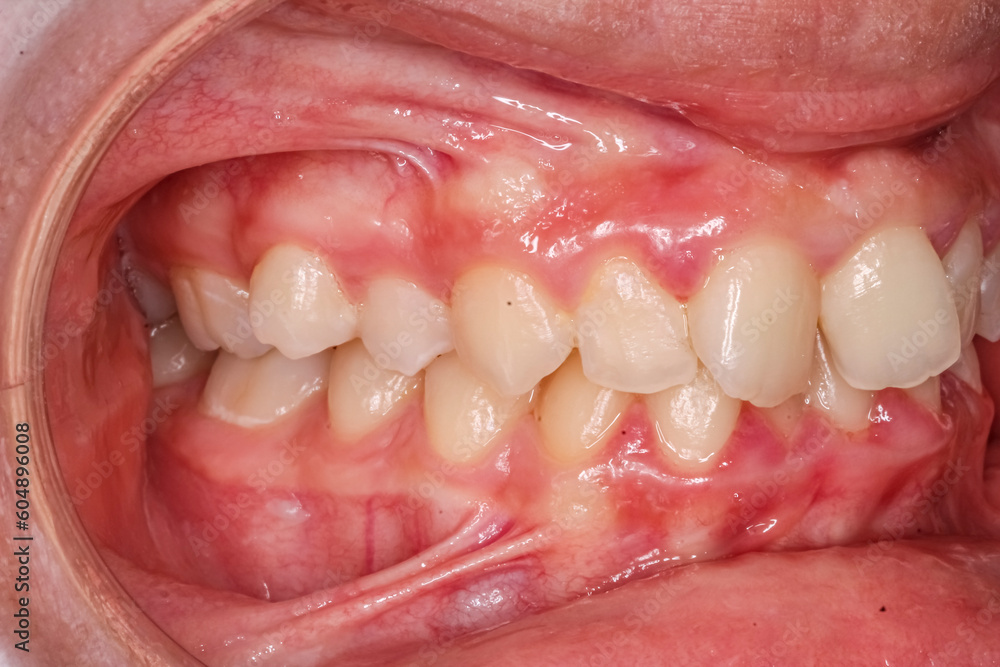

From stock.adobe.com

Oblique lateral view of dental arches, misaligned biting teeth with Misaligned Teeth Causing Cheek Biting There are several different types of misaligned bites, also called malocclusions. There may be an underlying issue with the upper or lower jaw. Malocclusion is the medical term for a bad bite, where someone’s teeth are misaligned and don’t make proper contact. Malocclusion is the most common reason for referral to an orthodontist. Uneven jaw occurs when the upper jaw,. Misaligned Teeth Causing Cheek Biting.